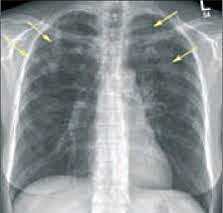

- Рентгенография легких. На снимках видны субплеврально расположенные одиночные (реже множественные, двусторонние) нечеткие затемнения средней интенсивности неправильной формы размером до 3-4 см. В окружении инфильтрата легочный рисунок усилен, тень корня легкого слегка расширена. Характерна быстрая динамика инфильтратов с миграцией по легочным полям и исчезновением не позднее 1-2 недель после обнаружения (чаще через 1-3 дня) без остаточной рубцовой деформации. При длительно поддерживающемся инфильтративном воспалении в ткани легких могут образоваться фиброзные очаги и кистозные полости.

- Рентгенологические исследования. Одним из наиболее информативных методов диагностики легочных эозинофилий считается рентгенография грудной клетки. На снимках обнаруживаются летучие (мигрирующие) эозинофильные инфильтраты в виде участков затемнения. При аллергическом бронхолегочном аспергиллезе могут быть видны бронхоэктазы, фиброз верхних отделов легких.

На рентгенограммах и КТ определяются участки инфильтрации различной плотности, расположенные по периферии, как правило, в верхних долях лёгких. В анализах крови выявляются значительное увеличение общего IgE, воспалительные изменения: повышение СОЭ, С-реактивного белка. Эозинофилия в крови определяется не всегда, но в БАЛ превышает 25%. В отличие от острой эозинофильной пневмонии длительность заболевания более 2 мес., возможны рецидивы.